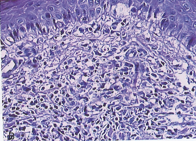

- 주근깨 -

정상피부

주근깨